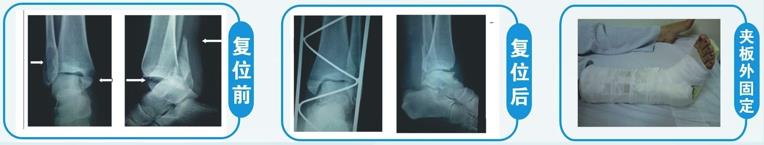

(2)踝部骨折 由于骨折靠近关节,若手术治疗对踝关节周围韧带等软组织损伤很大,容易造成术后关节功能恢复不良。科室对这类骨折有独特的复位和固定方法,复位理想,关节功能恢复良好。